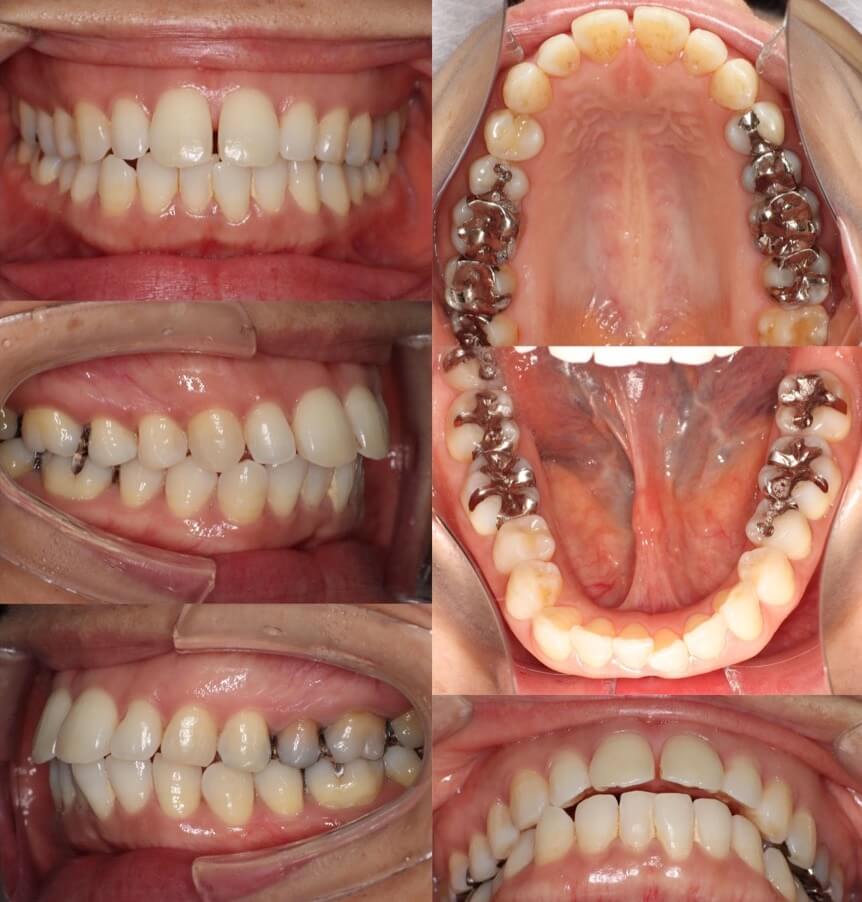

53代女性・ブリッジ補綴・マウスピース型装置

右下が2歯欠損しており、下の歯並びの正中も大きく右にずれているケースです。欠損部はブリッジ補綴を行う予定でしたので、スペースを開きすぎないように注意しながら上下歯列の正中線を近づけました。正中線は多少不一致が残ってしまったのですが、上の前歯も後退し、治療後は良好な歯列とかみ合わせになりました。

<症例概要>

主訴:上の前歯の前突

年齢・性別:50代女性

住まい:千葉県八千代市

症状:右下54番欠損・上顎前突・下顎右偏

治療方針:抜歯空隙閉鎖+下顎前歯唇側傾斜

補綴:右下⑦6⑤ブリッジ(一般歯科依頼)

治療装置:マウスピース型矯正装置(アライナー装置)

治療期間:1年7か月

アライナー枚数:42+31ステージ

リテーナー:上下フィックスタイプ+プレートタイプ

治療費用:990,000(税込)

代表的副作用:痛み・治療後の後戻り・歯根吸収・歯髄壊死・歯肉退縮

右下の抜歯欠損歯空隙にブリッジを作成できるよう1歯分以上(7.5mm)開かないように設定しました。